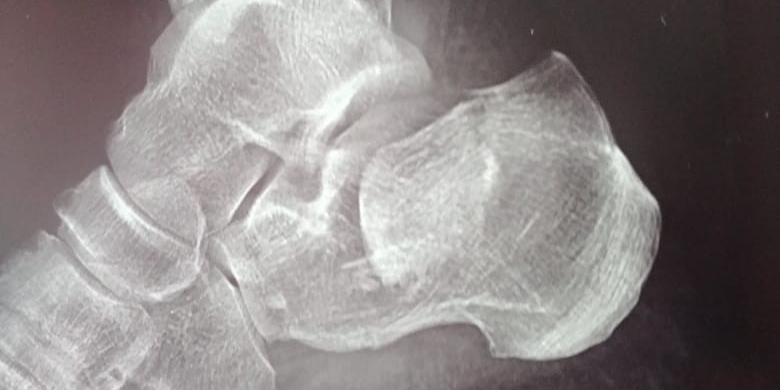

Перелом пяточной кости со смещением

Для того чтобы врач мог провести дифференциальную диагностику вида перелома пяточной кости и определить длину, высоту и угол пяточной кости, пострадавшему необходимо назначить рентгенологическое исследование стоп в аксиальном и боковая проекция.